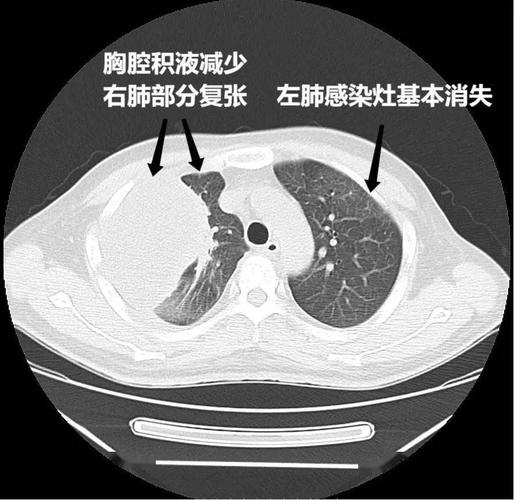

5月28日胸部ct可见右侧大量胸腔积液及左肺感染灶.